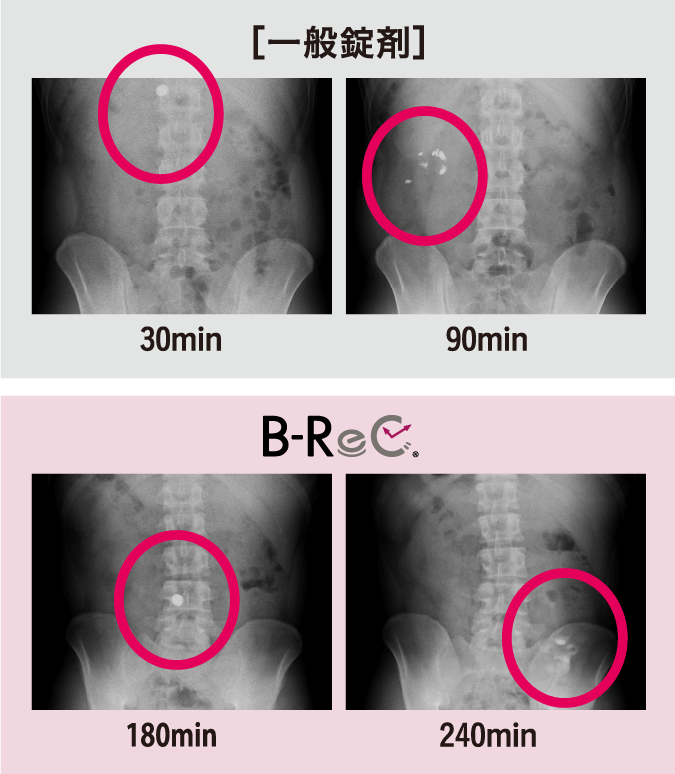

一般錠剤とB-ReC錠の体内動態を確認した。一般錠剤は90分以内に胃から十二指腸にかけて完全に崩壊したが、空腸崩壊型B-ReC錠では、摂取180分後の小腸上部(空腸)では崩壊せず240分後の小腸中部で崩壊した。

機能成分を消化管の目的部位に

デリバリーできる製剤であることが

証明された。 -